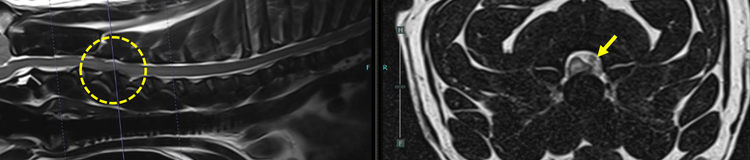

Rocio, along with the emergency on-call Specialist Anaesthetist Ffion Lloyd rushed Dougie to prep and blood gas analysis confirmed elevated CO₂ levels. Emergency anaesthesia was initiated to support ventilation, and the emergency on-call radiologist was called to carry out an immediate MRI. A scan of the cervical spine revealed a C3–C4 IVDE with associated epidural haemorrhage and significant spinal cord compression.

Magnetic resonance imaging (MRI) of the cervical spine revealed a C3-C4 intervertebral disc extrusion alongside epidural haemorrhage with marked left ventrolateral compression of the spinal cord. Generalised intervertebral disc degeneration was also noted.